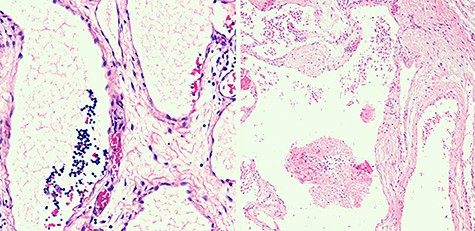

Macroscopically, cysts bigger than 2 cm3 were observed. Microscopically, the mass was composed by a variety of dilated lymph vessels involved in a fibrovascular stroma (Fig. 3). Diagnose of completely excised CL was done.